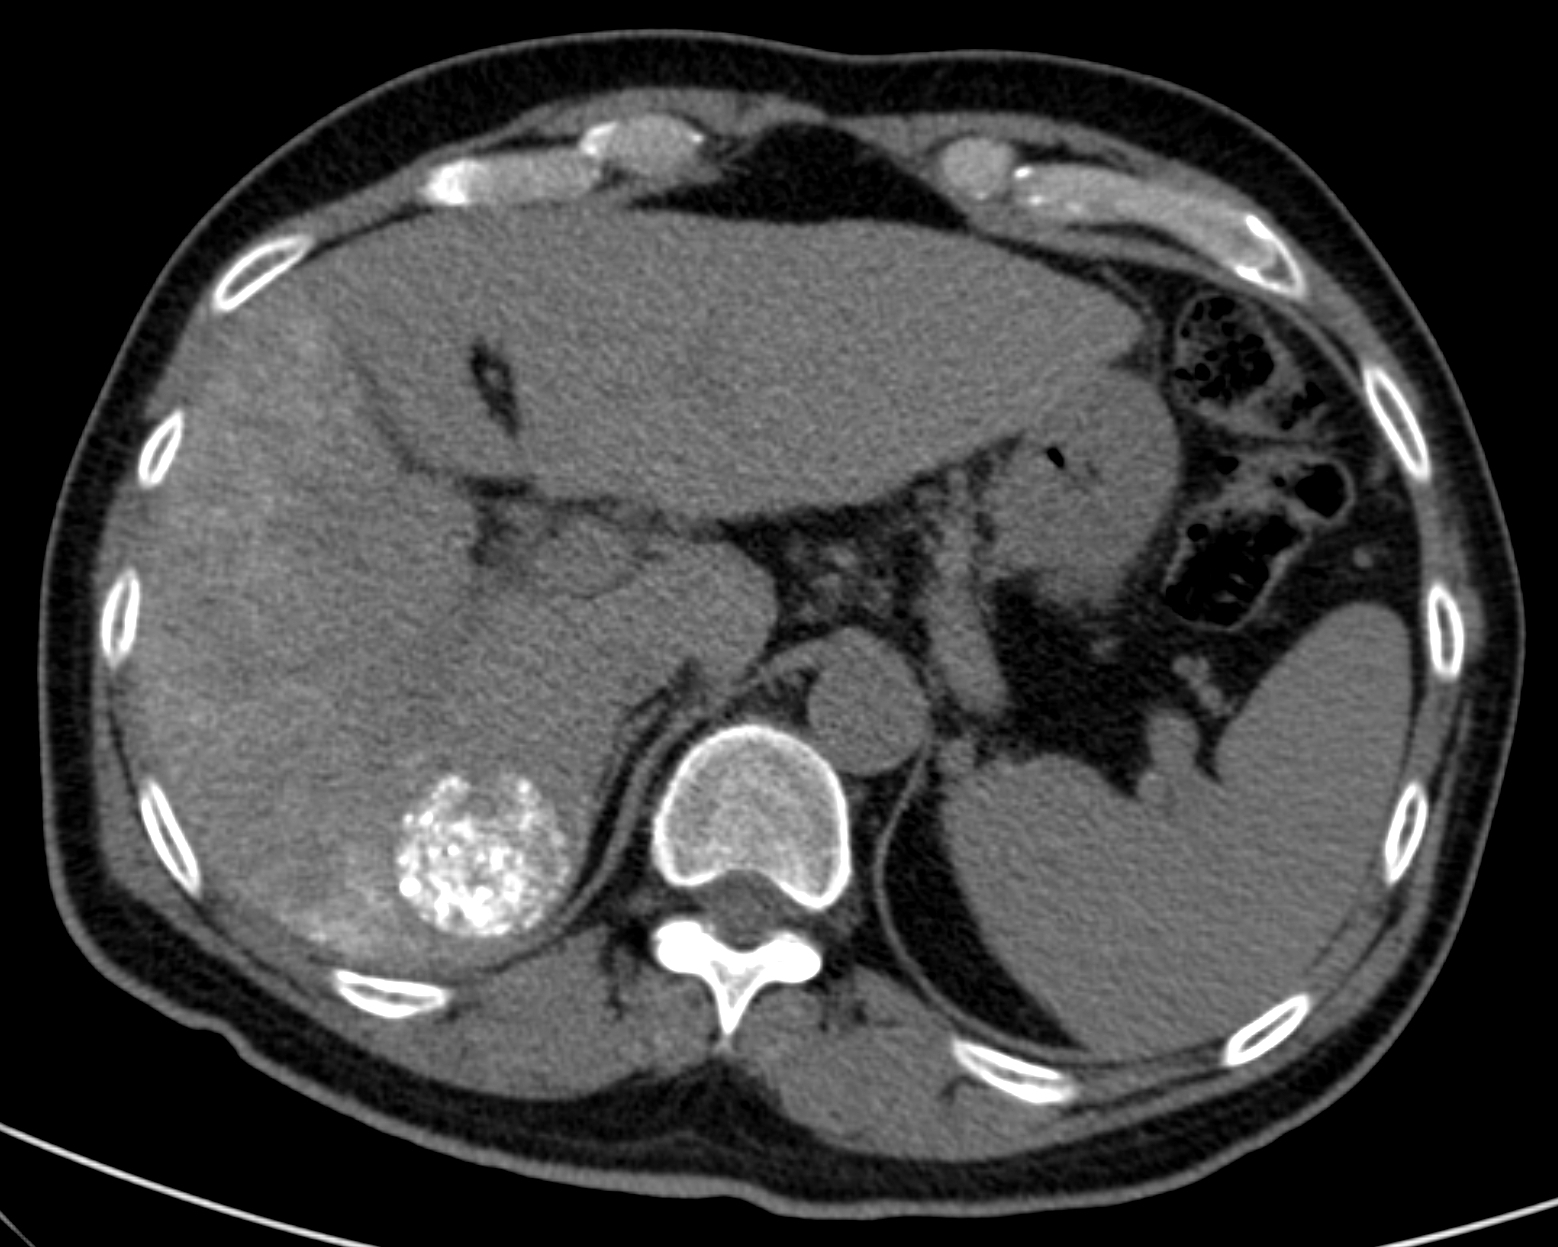

Very variable appearence forms can be observed by US and CT examinations from the early cyst in active phase to the cyst of the died parasite with a calcified wall (although the calcium appearing in the wall of the cyst does not mean that the parasite has unambiguously consumed) in case of an E. granulosus infection (Figure 15).

Figure 15: Echinococcus cyst in the liver, contrast enhanced CT